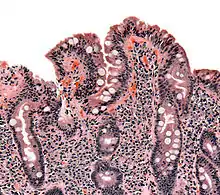

Coeliac Disease